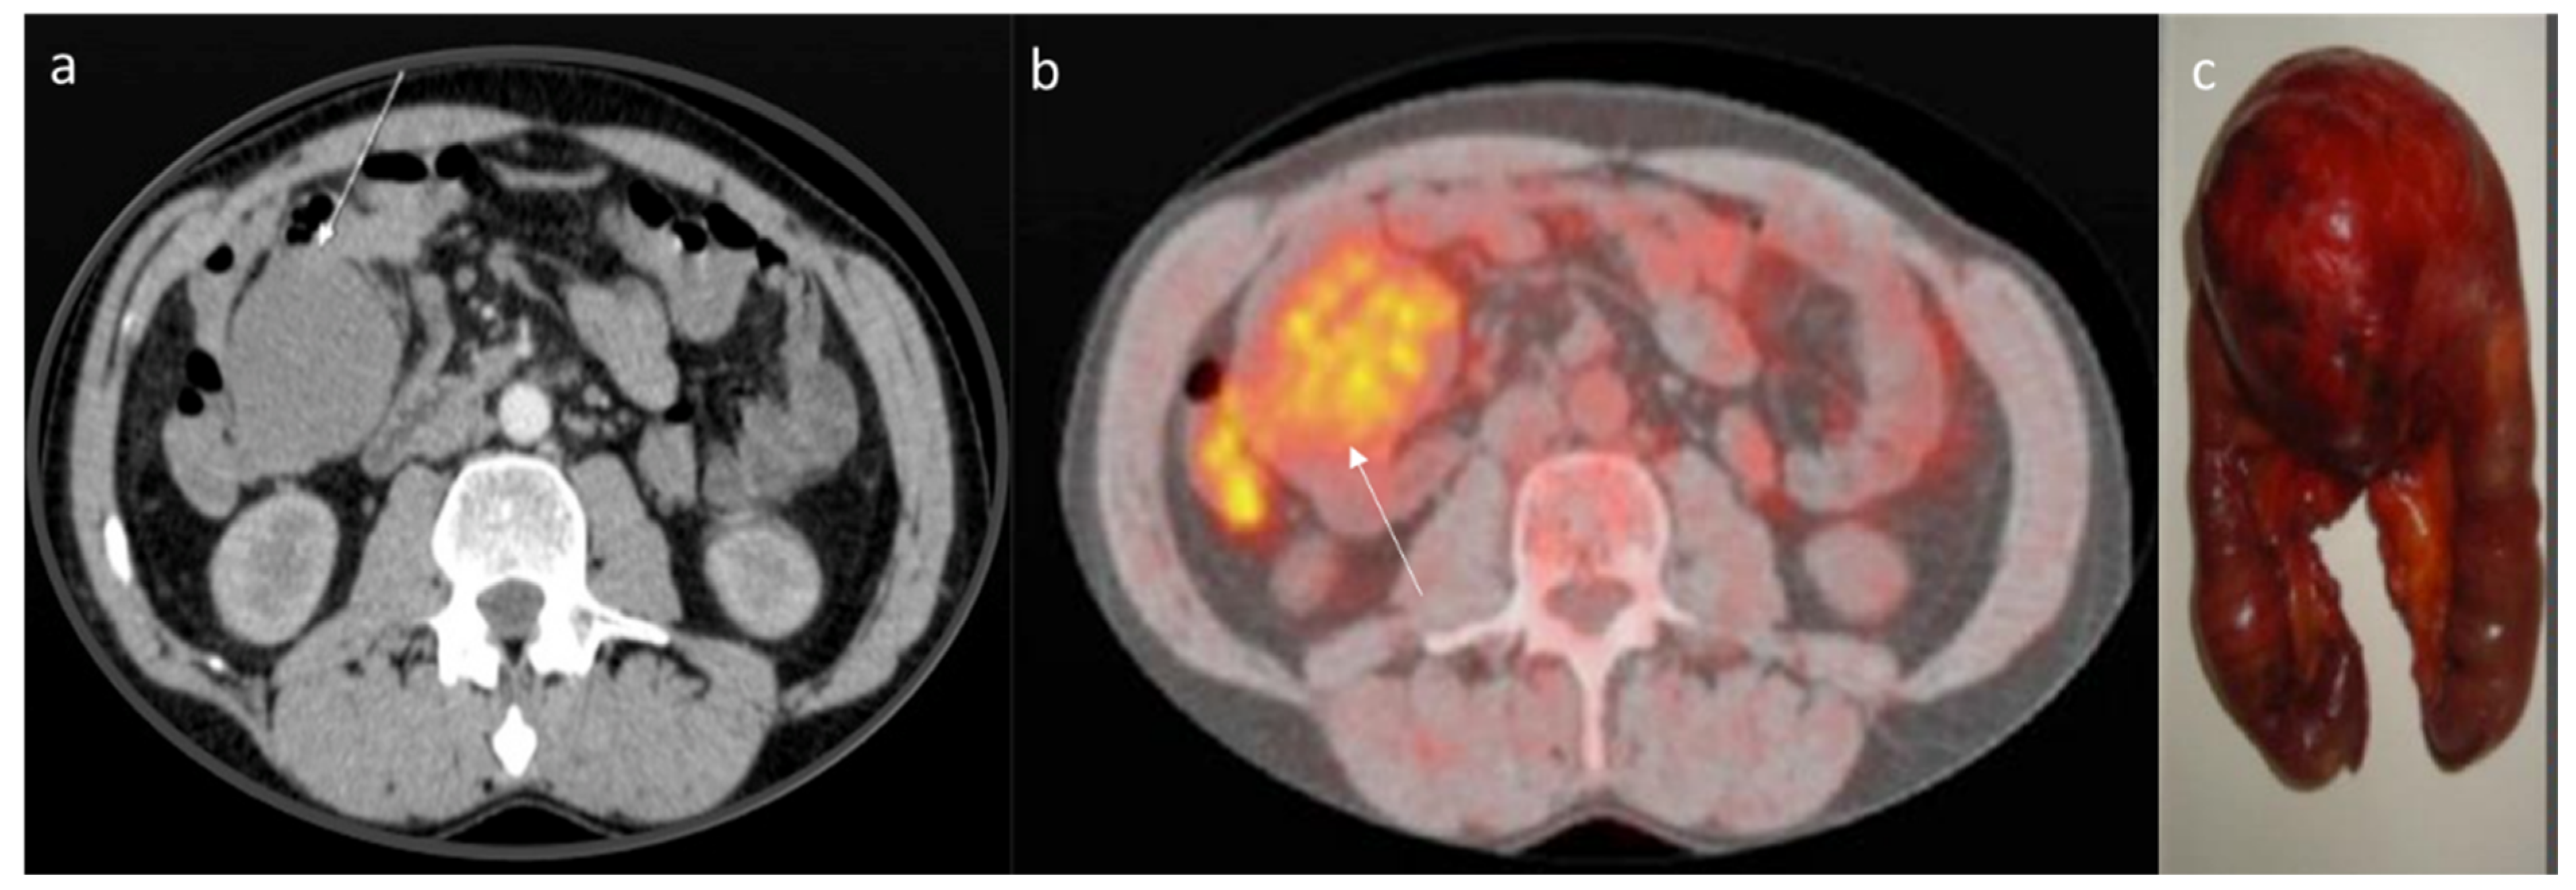

6. Computed Tomography Assessment